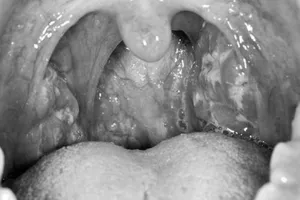

Viêm họng hạt nguy hiểm như thế nào?

05/12/2016 08:30